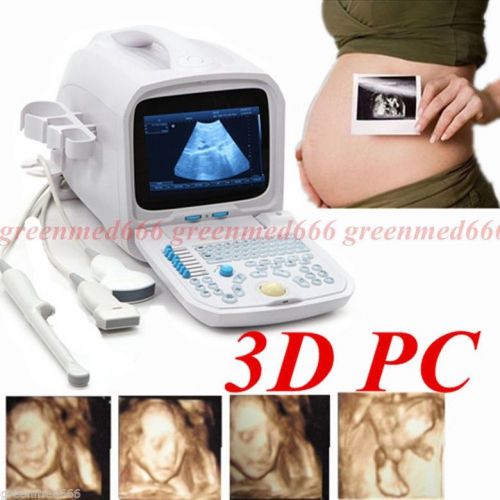

| Model | RUS-9000F |

3D PC Platform Full Digital Portable Ultrasound Scanner Machine +Convex Probe CE